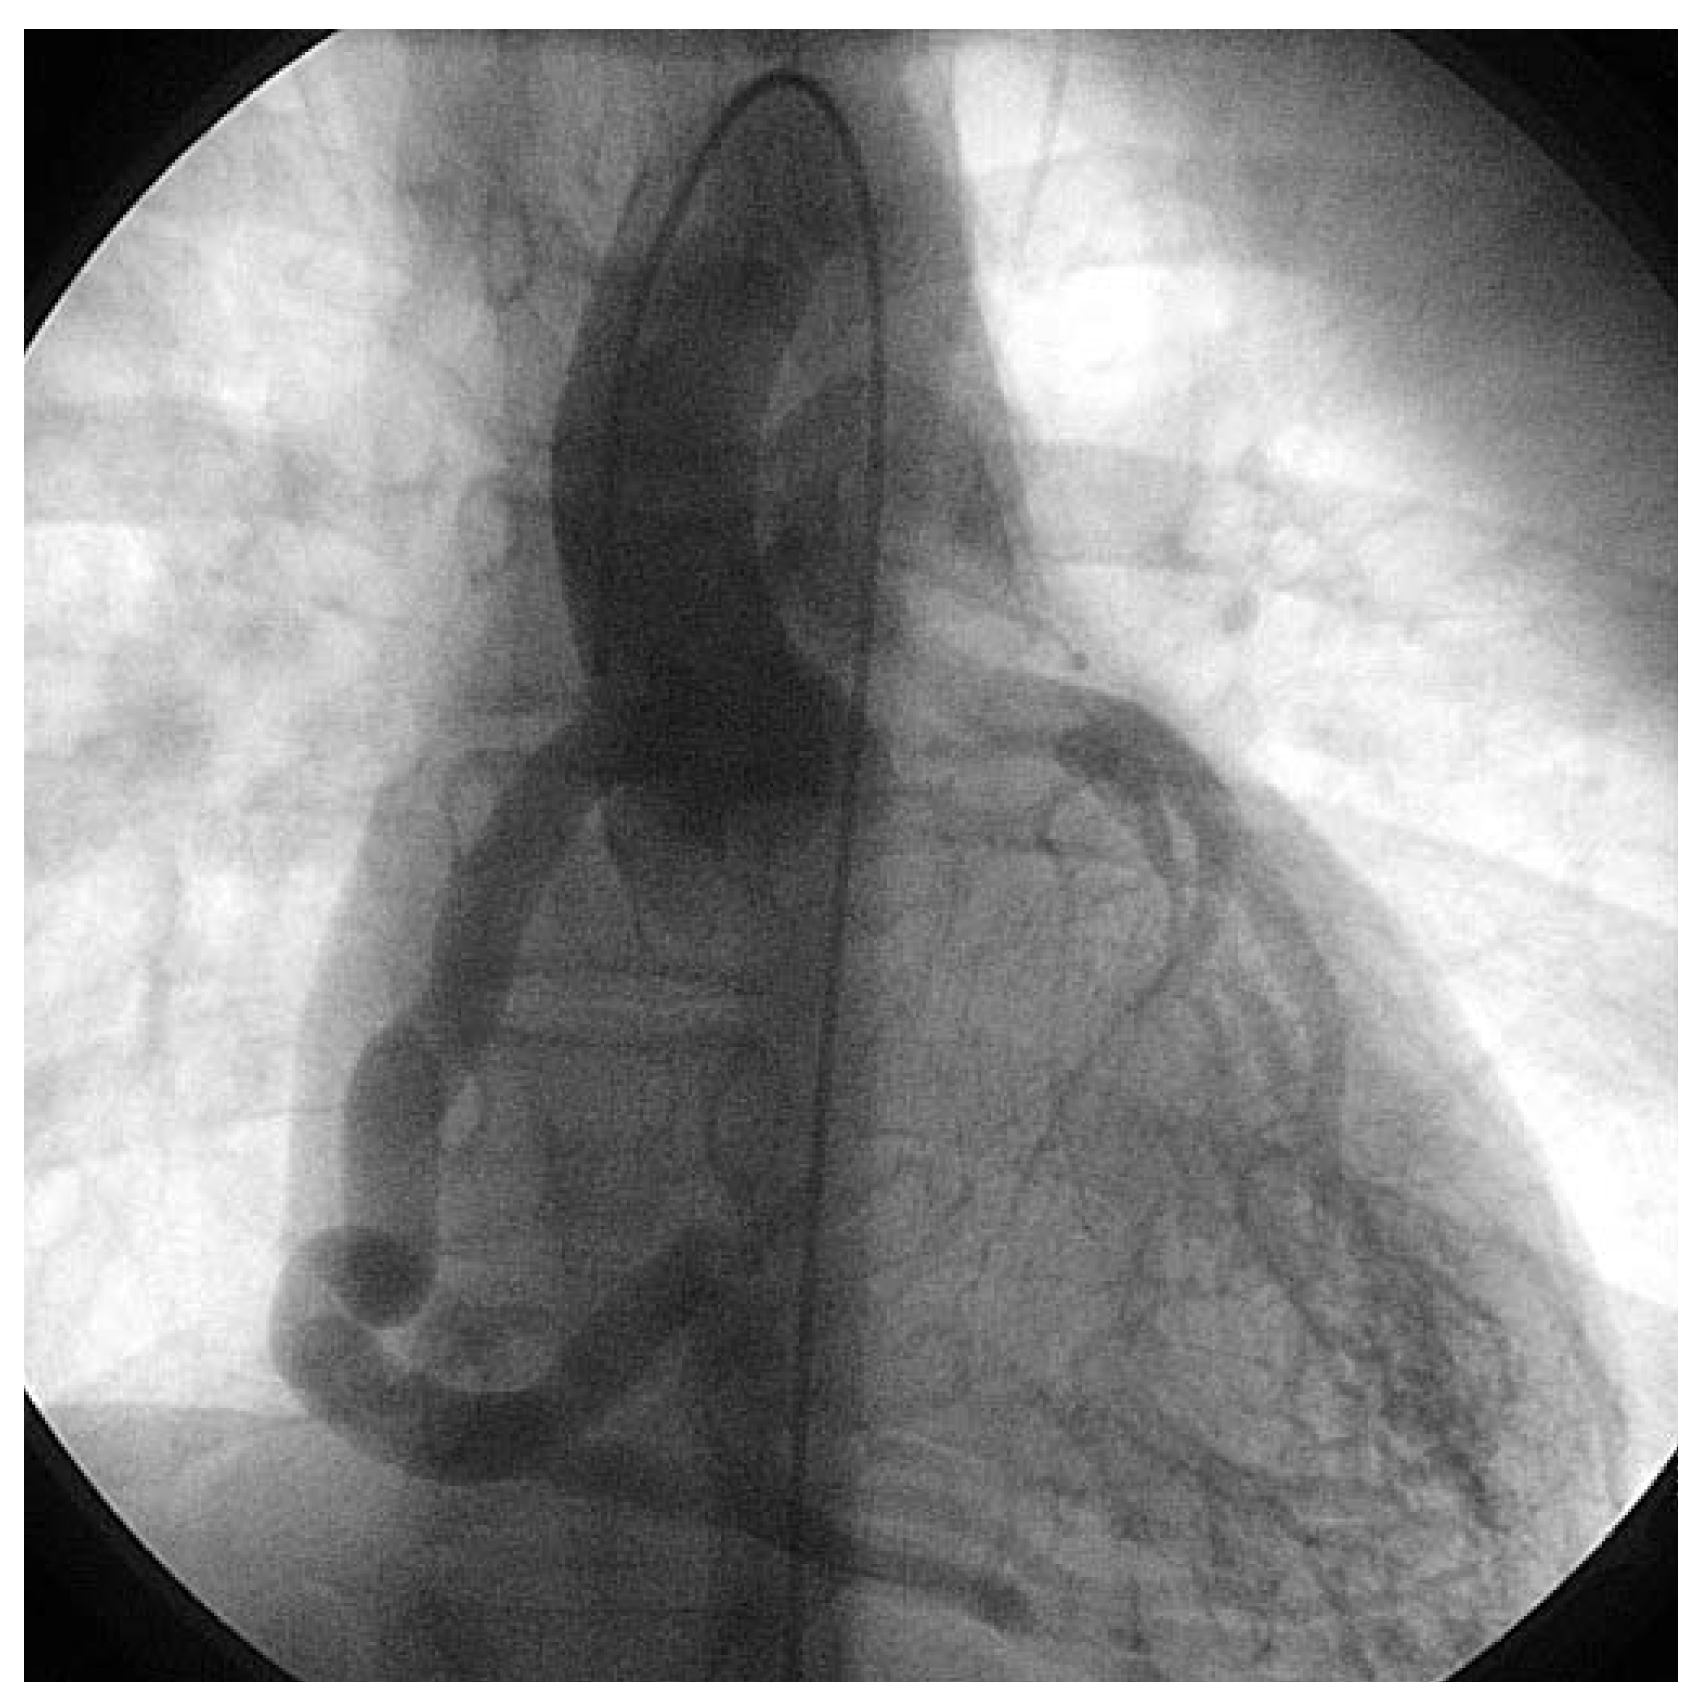

Asymptomatic Bland-White-Garland Syndrome in a 13-Year-Old Girl

Case report